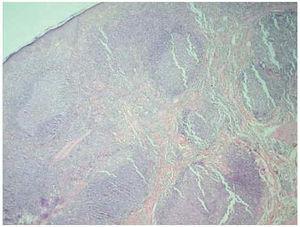

Se realizó estudio analítico con hemograma, bioquímica completa, coagulación, proteinograma e inmunoelectroforesis, hormonas tiroideas, estudio metabólico del hierro, determinación de vitamina B12 y ácido fólico, estudio inmunológico que incluía anticuerpos antiestreptolisina y anticuerpos antinucleares, analítica de orina y la detección de parásitos en heces, con todos los resultados completamente normales. La serología a Borrelia fue negativa. Entre los hallazgos patológicos destacaban sangre oculta en heces positiva, compatible con su enfermedad inflamatoria intestinal de base, una infección antigua por el virus del herpes simple tipo 1 (VHS-1) (IgM, IgG 1,65 mU/ml) y unos valores de IgE elevados (869 U/l). En el estudio histopatológico se observa en todo el espesor de la dermis, un infiltrado linfocitario que formaba folículos linfoides (fig. 2), con linfocitos de distintos tamaños y otros tipos celulares como eosinófilos, células plasmáticas y células fagocíticas con restos de núcleos linfocíticos en su interior. Este infiltrado no sólo respetaba la epidermis, sino que también dejaba una zona libre de dermis papilar. El estudio inmunohistoquímico mostró una positividad difusa para LCA; los centros germinales con CD20 (fig. 3) y el manto con CD3 (fig. 4) y Bcl 2.

Fig. 2.--Debajo de una epidermis adelgazada se obsevan infiltrados nodulares en toda la dermis formando folículos linfoides. (Hema-toxilina-eosina, ×40.)